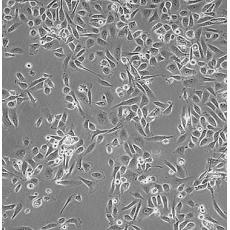

PC-3M

產品名稱 PC-3M

中文名稱 人前列腺癌細胞

組織來源 前列腺癌;骨髓轉移;男性

生長特性 adherent

培養基 RPMI-1640+10% FBS+1% P/S

形態特征 epithelial

傳代方法 1:2-1:4

培養條件 Atmosphere: Air, 95%; CO2, 5%。Temperature: 37℃